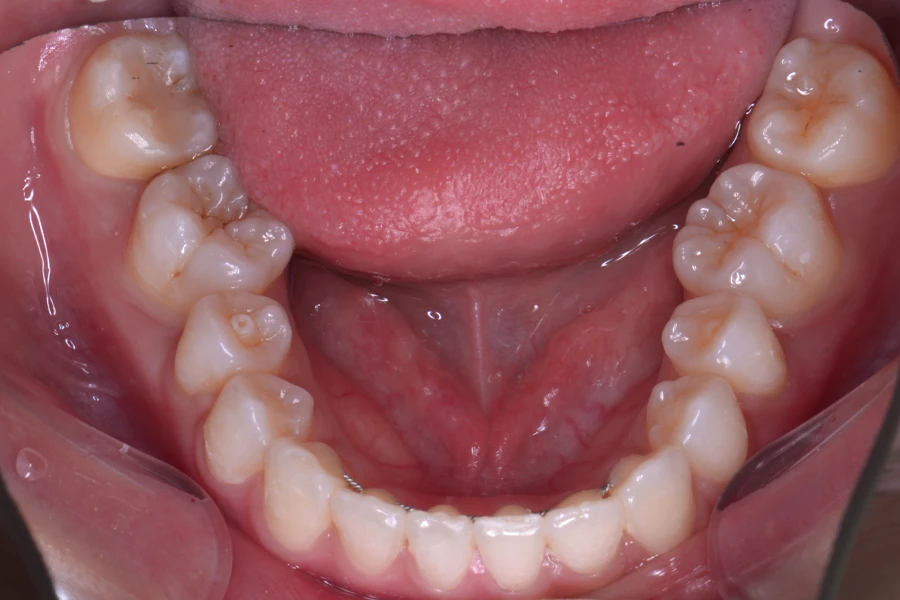

治療前

主訴 結婚式までに前歯を綺麗に整えたい

期間 10か月

費用 40万円(別途調整料)

デンタルローン80回 ¥5,800/月

治療内容 上下顎ラビアル矯正(表側矯正)

治療に伴うリスク 後戻り